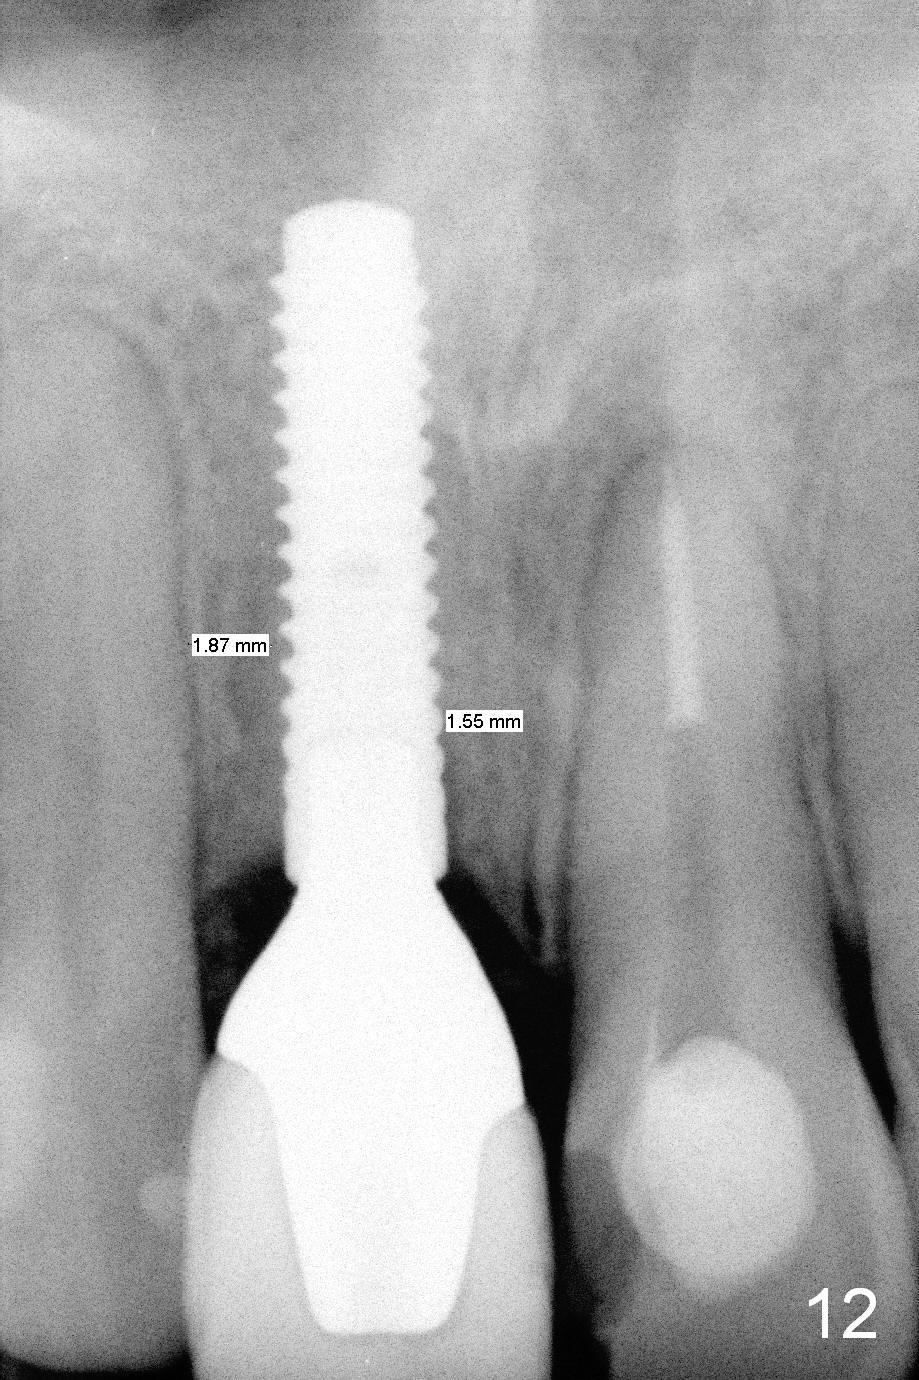

Fig.10 is a sagittal section of the implant (arrowheads: nasal floor). It is apparent that there is enough space (Fig.11,12 (PA)) for osteotomy (Fig.13 red lines: A: angled Titanium abutment). With the palatal mucoperiosteal flap attached the implant/bone segment, it is moved apically (Fig.14). Coronally the coronal portion is repositioned palatally while the apical portion buccally (Fig.15 arrows). Is the segment stable?